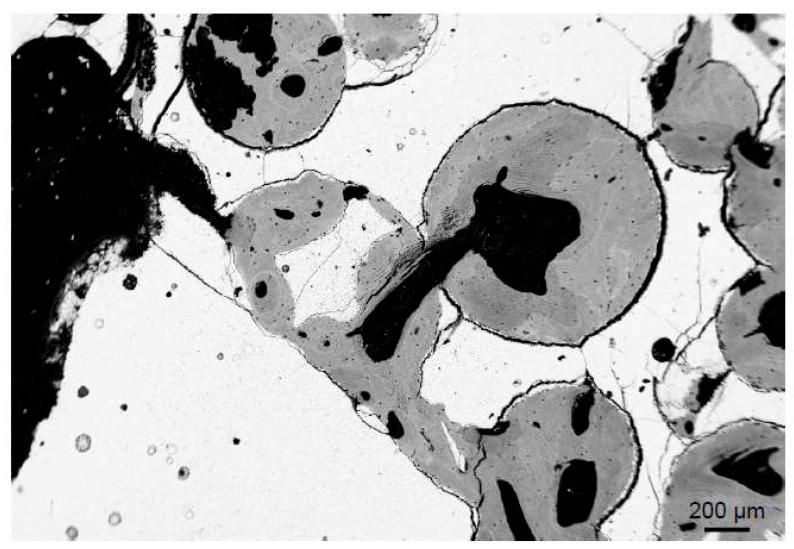

Bone grafts, i.e., autologous, allogeneic or synthetic bone substitute materials play an increasing role in reconstructive orthopedic surgery. While the indications and materials differ, it is important to understand the cellular mechanisms regarding their integration and remodeling, which are discussed in this review article. Osteoconductivity describes the new bone growth on the graft, while osteoinductivity represents the differentiation of undifferentiated cells into bone forming osteoblasts. The best case is that both mechanisms are accompanied by osteogenesis, i.e., bone modeling and remodeling of the graft material. Graft incorporation is mediated by a number of molecular pathways that signal the differentiation and activity of osteoblasts and osteoclasts (e.g., parathyroid hormone (PTH) and receptor activator of nuclear factor κβ ligand (RANKL), respectively). Direct contact of the graft and host bone as well as the presence of a mechanical load are a prerequisite for the successful function of bone grafts. Interestingly, while bone substitutes show good to excellent clinical outcomes, their histological incorporation has certain limits that are not yet completely understood. For instance, clinical studies have shown contrasting results regarding the complete or incomplete resorption and remodeling of allografts and synthetic grafts. In this context, a foreign body response can lead to complete material degradation via phagocytosis, however it may also cause a fibrotic reaction to the bone substitute. Finally, the success of bone graft incorporation is also limited by other factors, including the bone remodeling capacities of the host, the material itself (e.g., inadequate resorption, toxicity) and the surgical technique or preparation of the graft.